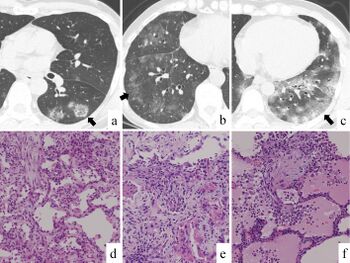

1349-7235-58-3509-g003.jpg

a-f) Chest computed tomography and histologic findings of viral pneumonia